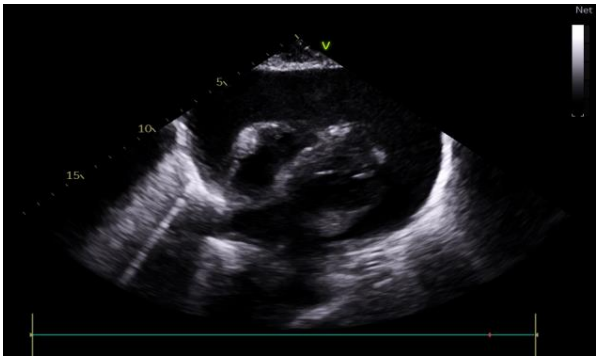

Transthoracic echocardiography revealed an abundant pericardial effusion, compressing the right cavities in proto-diastole, with significant flow variation (figure2).

27 mm >> OD.

32 mm >> RV.

26 mm >> LV.

16 mm >> OG.

26 mm >> Apex.

Inferior vena cava dilated to 23 mm;(figure3).

Figure 2: subcostal view showing a large pericardial effusion

Figure 3: subcostal view showing the dilation of the inferior vena cava